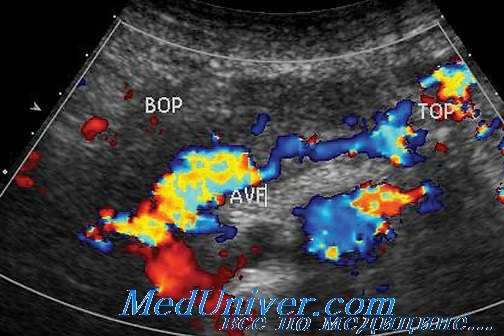

В диагностике тромботических осложнений определенную помощь могут оказать допплеросонография и ЯМР, подтверждающие снижение кровотока в питающих трансплантат сосудах, а в ряде случаев — ангиография.